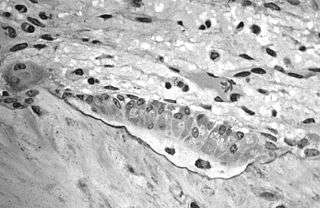

Light micrograph of osteoblasts, several displaying a prominent Golgi apparatus, actively synthesizing osteoid containing two osteocytes.

The underlying mechanism in all cases of osteoporosis is an imbalance between bone resorption and bone formation. In normal bone, matrix remodeling of bone is constant; up to 10% of all bone mass may be undergoing remodeling at any point in time. The process takes place in bone multicellular units (BMUs) as first described by Frost & Thomas in 1963.[74] Osteoclasts are assisted by transcription factor PU.1 to degrade the bone matrix, while osteoblasts rebuild the bone matrix. Low bone mass density can then occur when osteoclasts are degrading the bone matrix faster than the osteoblasts are rebuilding the bone.[75]

The three main mechanisms by which osteoporosis develops are an inadequate peak bone mass (the skeleton develops insufficient mass and strength during growth), excessive bone resorption, and inadequate formation of new bone during remodeling. An interplay of these three mechanisms underlies the development of fragile bone tissue.[26] Hormonal factors strongly determine the rate of bone resorption; lack of estrogen (e.g. as a result of menopause) increases bone resorption, as well as decreasing the deposition of new bone that normally takes place in weight-bearing bones. The amount of estrogen needed to suppress this process is lower than that normally needed to stimulate the uterus and breast gland. The α-form of the estrogen receptor appears to be the most important in regulating bone turnover.[26] In addition to estrogen, calcium metabolism plays a significant role in bone turnover, and deficiency of calcium and vitamin D leads to impaired bone deposition; in addition, the parathyroid glands react to low calcium levels by secreting parathyroid hormone (parathormone, PTH), which increases bone resorption to ensure sufficient calcium in the blood. The role of calcitonin, a hormone generated by the thyroid that increases bone deposition, is less clear and probably not as significant as that of PTH.[26]

Trabecular bone (or cancellous bone) is the sponge-like bone in the ends of long bones and vertebrae. Cortical bone is the hard outer shell of bones and the middle of long bones. Because osteoblasts and osteoclasts inhabit the surface of bones, trabecular bone is more active and is more subject to bone turnover and remodeling. Not only is bone density decreased, but the microarchitecture of bone is also disrupted. The weaker spicules of trabecular bone break ("microcracks"), and are replaced by weaker bone. Common osteoporotic fracture sites, the wrist, the hip and the spine, have a relatively high trabecular bone to cortical bone ratio. These areas rely on the trabecular bone for strength, so the intense remodeling causes these areas to degenerate most when the remodeling is imbalanced. Around the ages of 30–35, cancellous or trabecular bone loss begins. Women may lose as much as 50%, while men lose about 30%.[28]